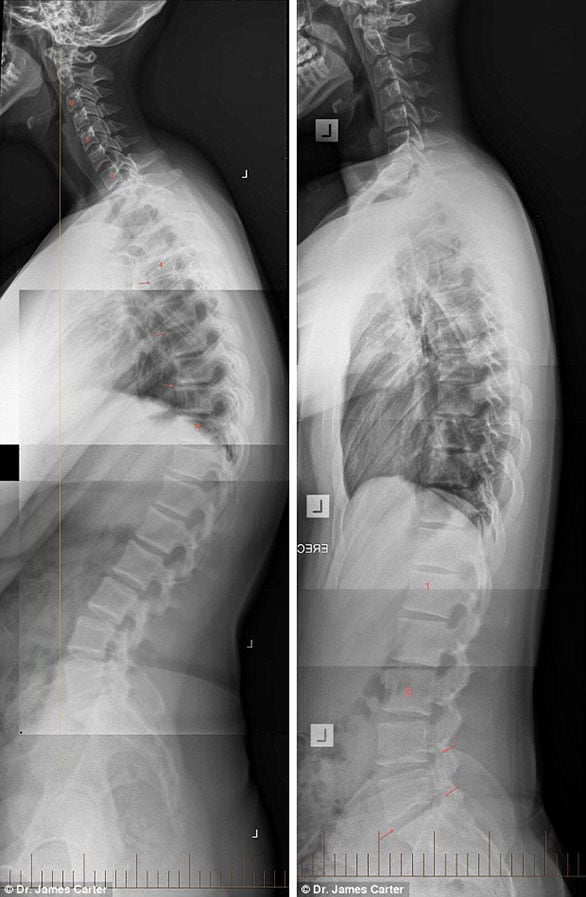

وأرفق الطبيب تحذيراته بمجموعة من صور الأشعة السينية لبعض الحالات المصابة بمرض التنكسية في العمود الفقري نتيجة استعمال الهاتف الذكي لفترة طويلة، توضح تشوهات وآلام في الرأس والرقبة والكتف والظهر.